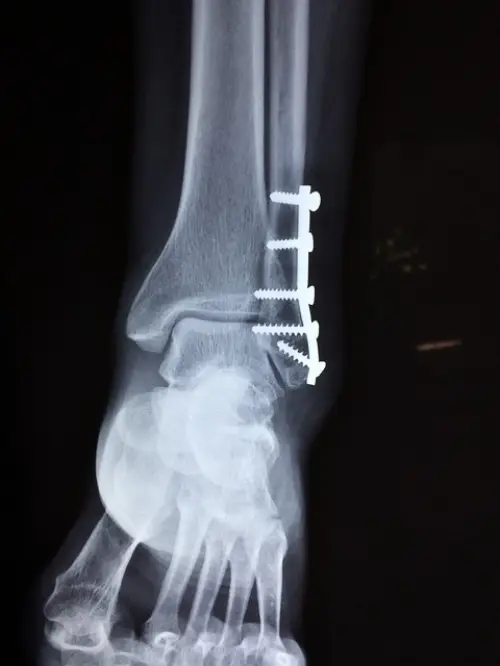

3단계: 인대 완전 파열

가장 심각한 단계인 3단계 염좌는 인대가 완전히 파열된 상태입니다. 극심한 통증과 함께 심한 부종, 멍이 나타나며 발목에 전혀 체중을 실을 수 없습니다. 발목이 불안정해지고 심할 경우 변형이 관찰되기도 합니다. 이 경우에는 전문적인 의학적 치료가 필수이며, 수술적 치료가 필요할 수 있습니다. 수술 후에는 장기간의 회복과 재활 치료가 진행되어야 하며 회복 기간은 6주에서 3개월 이상 걸릴 수 있습니다.

상기 증상들이 나타났을 때는 X-ray, MRI 등 영상 검사를 통해 인대 파열 정도, 골절 여부, 주변 조직 손상 등을 정확히 확인하는 것이 중요합니다. 이를 통해 적절한 치료계획을 세울 수 있습니다.